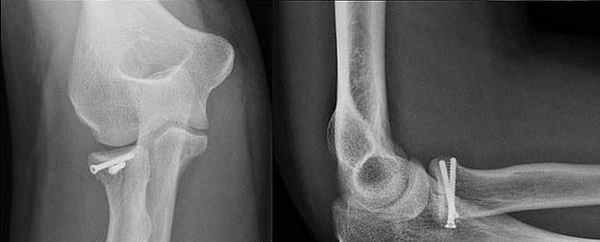

При переломе венечного отростка остеосинтез выполняют 3,5 мм винтом. Для остеосинтеза перелома головки лучевой кости применяют фиксацию малым спонгиозным винтом.

Остеосинтез головки лучевой кости и венечного отростка локтевой винтами.